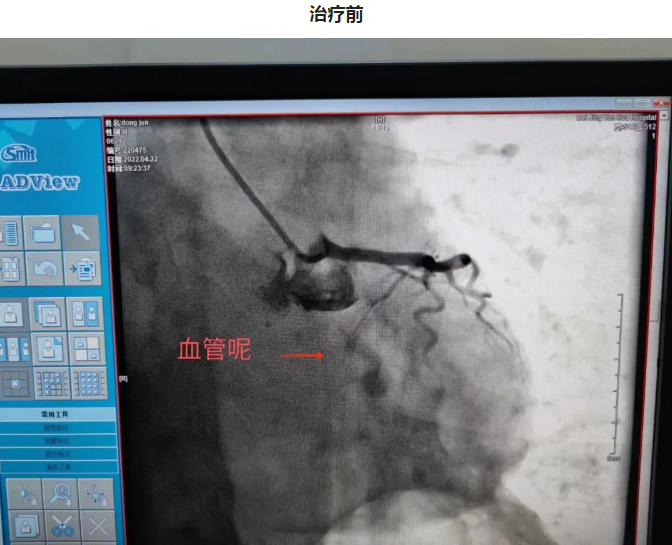

第二日晨,3年前冠脉置入一枚支架的62岁的董大爷干农活时突发咽部紧缩感,伴胸闷不适,持续不缓解,呼叫120送至我院急诊,血压75/56mmHg,急诊考虑急性下壁心肌梗死,心源性休克,急诊立即排查新冠肺炎的同时联系我科,做好术前准备后急送至导管室,冠脉造影可见原支架位于左主干至前降支近段,回旋支消失不见,李钢主任反复尝试后找到回旋支开口,并给予成功重新开通血管,患者血流恢复,症状缓解,但血压持续偏低,考虑患者心源性休克,给予患者置入IABP(主动脉内球囊反搏)作为辅助,患者心功能逐渐恢复,治愈出院。